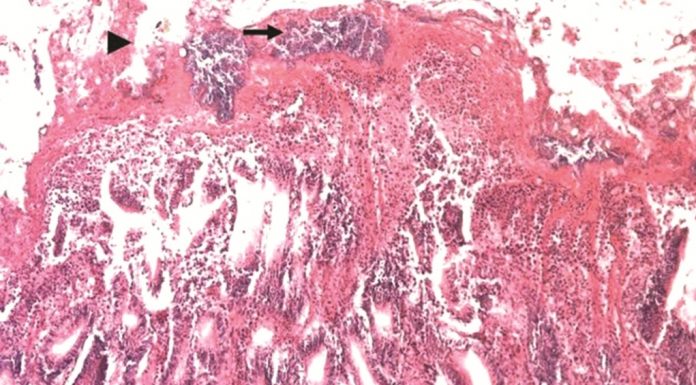

POULTRYINDONESIA, Jakarta - Pada ayam pedaging, penyakit ini dapat ditemukan dalam bentuk akut dan ringan. Bentuk akut ditandai oleh adanya kematian mendadak tanpa didahului oleh gejala klinik tertentu. Sedang, bentuk ringan ditandai oleh adanya ayam yang bergerombol, bulu berdiri, depresi, dan penurunan atau kehilangan nafsu makan. Ayam yang terinfeksi biasanya mengalami diare dan mortalitas yang bervariasi. Penyakit in mengalami...